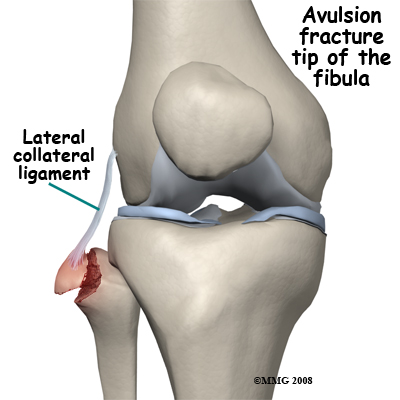

Avulsion fractures are common and easily missed. This may involve the lateral epicondyle, a Segond capsular avulsion or occasionally there is a tell tale avulsion of the tip of the fibular head indicating distraction of the lateral ligaments, this is termed the "Arcuate sign".